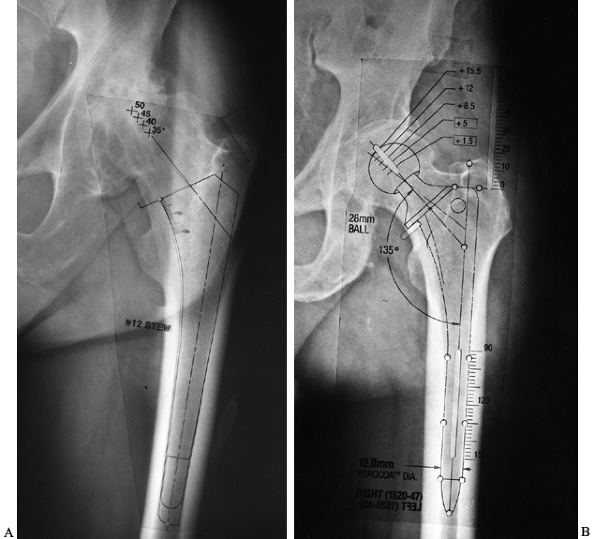

radiograph. Properly sized cemented implants leave room for a cement

mantle of appropriate size and also leave adequate cancellous bone

after broaching for cement interdigitation (Fig. 105.7). Most templates show the outline

of the broach corresponding to each implant size, making it possible to

visualize the amount of intramedullary cancellous bone left after

broaching. Choose uncemented implants to fit and fill the part of the

femur in which that particular implant obtains fixation (Fig. 105.8A and Fig. 105.8B).

![]() |

Figure 105.7. AP radiograph of the hip with template for a cemented femoral component. The template shows the broach envelope (a dotted outline, which simulates the minimum cement mantle), as well as the femoral component (solid line).

Note that the implant size chosen should leave some cancellous bone behind after broaching to provide for cement interdigitation. |

Figure 105.8. A:

AP hip radiograph template for a proximally coated uncemented stem. Note that with this type of implant, priority is given to obtaining a good fit in the metaphyseal and metaphyseal-diaphyseal junction areas. B: AP hip radiograph with a template for an extensively porous-coated uncemented stem. Note that with this type of implant, priority is given to getting a good fit in the diaphysis. |